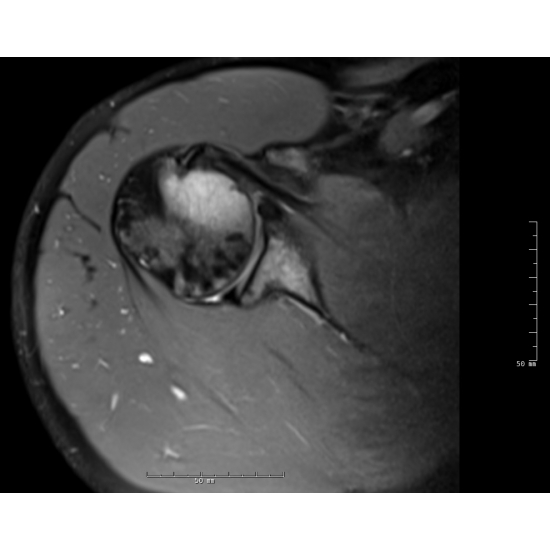

| A Hairy Case Of Recurrent Right Shoulder Pain - Page #3 | |||